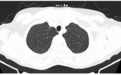

因为担心,王女士今年的例行体检果断选择了胸部 CT,结果发现右肺上叶尖后段胸膜下磨玻璃结节影(0.6 cm × 0.5 cm)(见图 1),她无吸烟史,没有肿瘤家族史,下一步她该怎么办呢?手术还是随访观察?

图 1